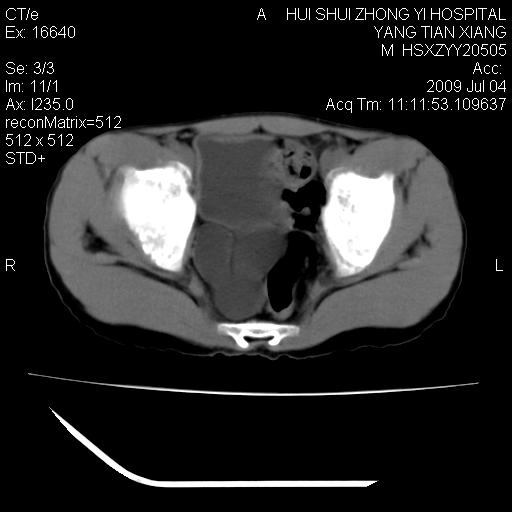

肝右叶胆管内见条状高密度影,脾脏增大,双肾上腺无异常;右肾正常结构消失,其实质内见类圆形低密度灶,ct值范围0-6hu,界清,右输尿管全程伴行多发低密度灶,界清,膀胱壁增厚,腹盆腔未见确切肿大淋巴结。

考虑:1、肝内多发胆管结石并肝内胆管扩张。2、右肾、输尿管多发脂肪瘤,多发平滑肌瘤?建议ct增强检查。4、膀胱壁增厚。

1)考虑右侧巨输尿管畸形。2)肝内胆管多发性结石。3)脾大。

右侧巨输尿管并神谕积水,左肾代偿性肥大,脾大,肝内胆管多发结石并胆管扩张。